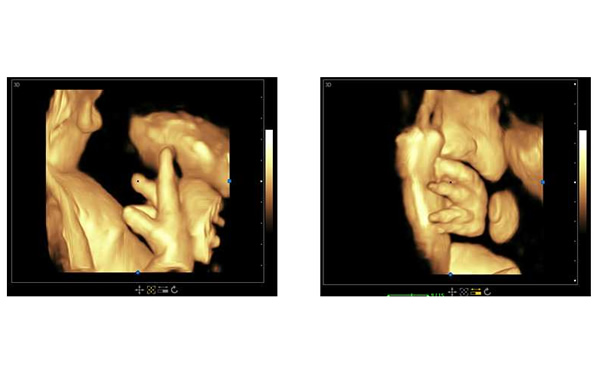

孕期B超檢查三個階段,大為醫(yī)療高端彩超孕期胎兒顯示

懷孕中期,通過B超檢查可以大概知道子宮內(nèi)的胎兒生長的情況。并且可以通過B超了解到孩子的身體組織器官有沒有畸形。如果孩子出現(xiàn)了畸形,根據(jù)醫(yī)生的建議或者是相關(guān)的規(guī)定來決定是不是不再繼續(xù)妊娠。

這個時候做B超就可以了解到子宮內(nèi)羊水的含量,孕婦體內(nèi)的胎盤是不是處于正常的狀態(tài),以及孩子有沒有出現(xiàn)臍帶繞頸的情況。如果子宮內(nèi)的羊水不夠,胎盤出現(xiàn)鈣化的情況,或者孩子出現(xiàn)了臍帶繞頸的現(xiàn)象,那么就要加以重視,好好咨詢醫(yī)生。B超還可以知道胎兒頭徑的多少以及胎兒骨骼的生長情況,以此來大概判斷出孩子到底有多重,準(zhǔn)確得知胎寶寶的在子宮中的位置,并判斷孩子是不是可以自然生產(chǎn)出來。此外,B超檢查還可以知道胎兒臍帶血流參數(shù),通過此參數(shù)可以知道胎兒在子宮內(nèi)是不是正常地生長。

醫(yī)院用高端三維多普勒、4D成像技術(shù)的彩超可以參考大為醫(yī)療的高端彩超。